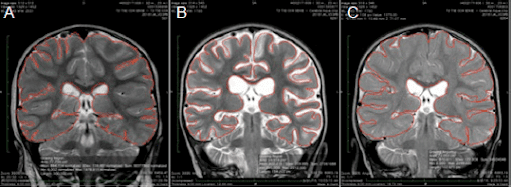

Hyperbaric Oxygen Treatment—From Mechanisms to Cognitive Improvement

HBOT IMPROVEMENT ON BRAIN FUNCTIONS